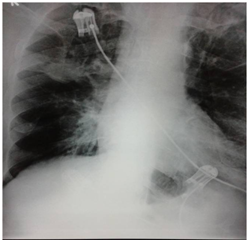

Fifty two year old Iraqi national presented with altered sensorium. He had 25 pack years of smoking history but without any symptoms or treatment related to chronic obstructive pulmonary disease. There was no other medical or surgical history as well. Physical examination revealed normal vital signs. Abdomen, cardiovascular and respiratory system were unremarkable. On neurological assessment he qualified Glassgow Coma Scale of 12/15. However there was no focal neurological deficit. Haemogram, liver and kidney biochemistries were acceptable. Computerised tomography (CT) of head did not reveal any abnormality. Lumbar puncture for cerebrospinal fluid (CSF) examination was performed. It revealed high pressure with mononuclear pleocytosis, high protein and below normal sugar. India ink preparation, smear for acid fast bacilli and gram stain were unyielding. Cytology revealed fair number atypical cells singly and in clusters, larger in size with high nucleo-cytoplasmic ratio, coarse chromatin and scanty to moderate cytoplasm with few binucleate forms. Features highly suggestive of metastasis. This lead to search for primary site of malignancy. Chest skiagram (Figure 1) of the patient showed rounded opacity in right upper zone of lung. Contrast enhanced CT scan of chest was requested and it unvield speculated mass lesion in the upper lobe of right lung (Figure 2). Videobronchoscopy examination revealed abnormal findings in the right upper lobe. Mucosa appeared swollen with rough surface but without any endobronchial growth. Rest of the bronchial tree was normal. Bronchial washings, endobronchial and transbronchial biopsies were obtained from the right upper lobe. Histopathology of biopsy was positive for non small cell carcinoma of the lung subtype adenocarcinoma (Figure 3).

Figure 2 CT Scan of thorax: Right upper lobe mass.